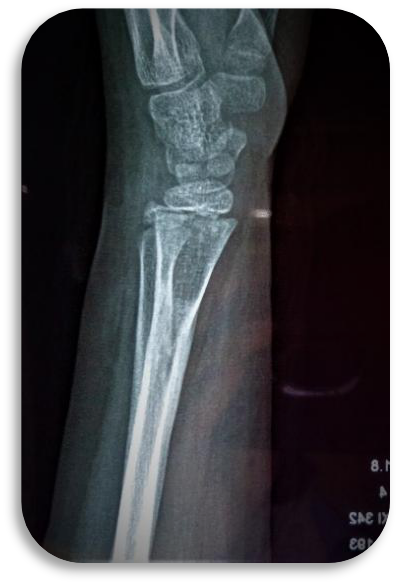

科室设置四个亚专业:创伤骨科以微创开展复杂骨折与多发伤救治,实现骨折愈合与功能恢复同步;手足显微外科凭精细显微操作,开展断指(肢)再植、血管神经损伤修复,游离皮瓣移植创面修复,各类手足畸形矫治;关节与骨质疏松组遵循阶梯化治疗,开展保关节、微创关节置换及各类关节翻修手术,骨质疏松专业实现骨质疏松全生命周期管理,规范抗骨质疏松治疗切实降低骨折风险,改善骨质健康;运动医学专业以关节镜微创技术为核心,诊治各种运动系统损伤,结合康复疗法助力患者重返运动。